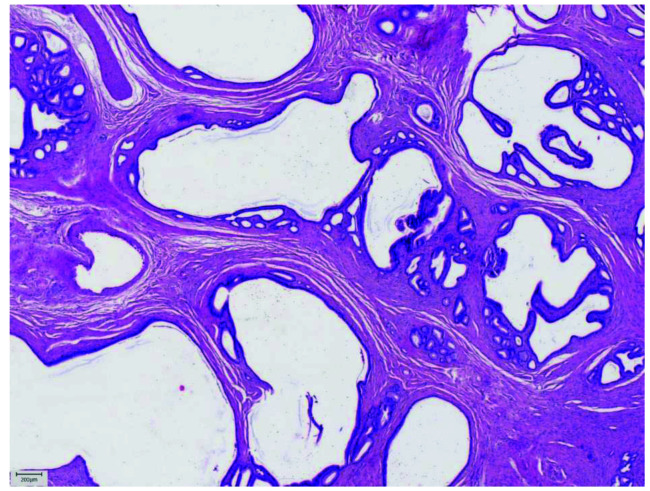

Pancreatic heterotopia is a relatively rare condition that implies pancreatic tissue anatomically separated from the main gland, showing no vascular or ductal continuity. It is known to occur in many sites of gastrointestinal tract, with stomach being the most common one. This case is of great interest because ectopic pancreatic tissue in jejunal wall presented as bowel obstruction. The aim of this article is to provide a review of clinical, histopathologic and immunohistochemical features of ectopic pancreatic tissue in jejunum, emphasizing the possible diagnostic pitfalls in gastrointestinal tract, especially in its upper parts. Knowing the most common locations, imaging features and histopathologic criteria, the diagnosis of pancreatic heterotopia could be successfully set preoperatively. Associated complications are various and sometimes difficult to handle, so accurate and precise diagnosis, as well as surgical resection, is often needed.

Abstract Image